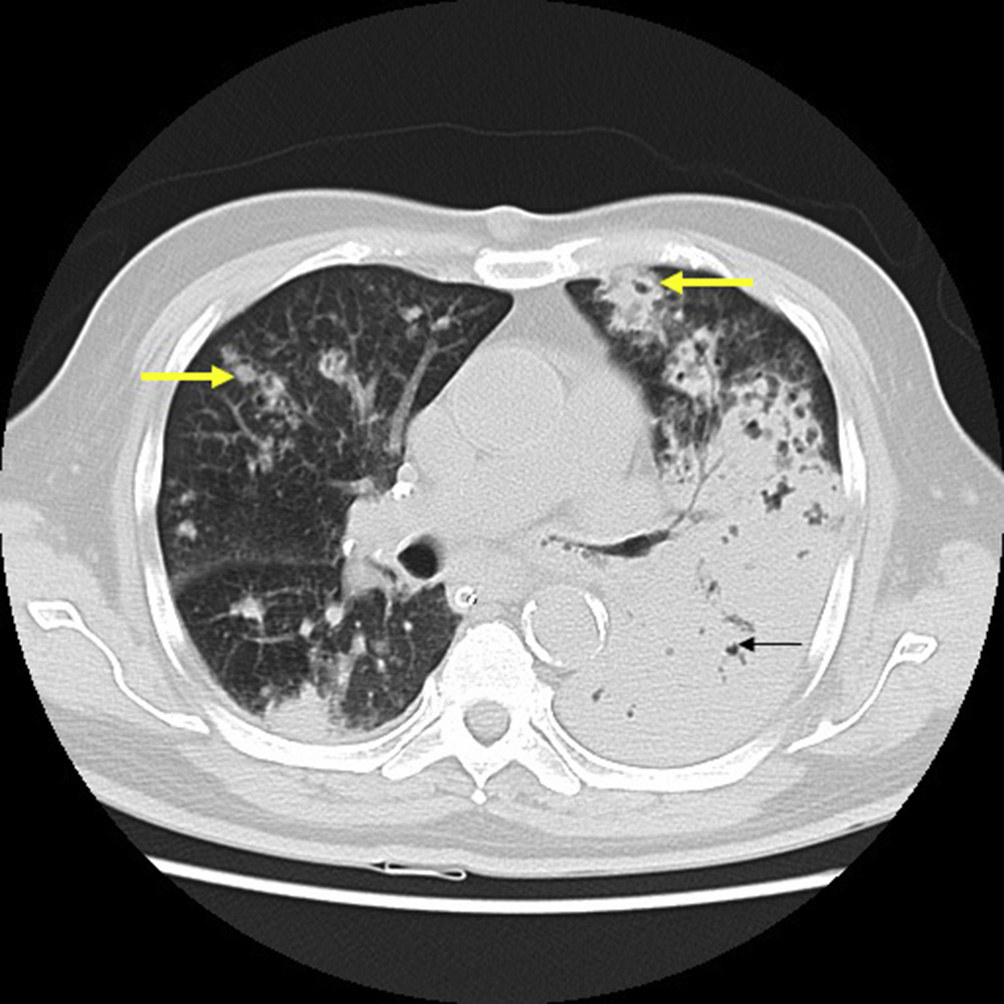

Fig. 2. CT transverse section shows large area of consolidation (arrow) in superior segment of left lower lobe. Fig. 3. CT transverse section (lung window) shows bilateral nodular lesions (yellow arrows) and subtle air bronchogram in large area of consolidation (thin arrow) on left.

He was initiated on ceftriaxone, azithromycin and non invasive ventilation for mild ARDS(Acute Respiratory Distress Syndrome). On day 4 of hospital stay, his breathing mechanics worsened and he was initiated on mechanical ventilation in view of worsening ARDS and pneumonia. Endotracheal aspirate culture initially revealed Staphylococcus aureus which was subsequently turned out to be contaminant. To rule out pulmonary tuberculosis two samples were sent for AFB smear (Acid Fast Bacillus)examination and were found to be negative. Mycobacterial culture was sent. CT thorax on day 8 showed bilateral extensive areas of consolidation (Figs. 2e4) with multiple small cavitating nodules (Fig. 5). Special stain for Nocardia was done on the broncho-alveolar lavage e Kinyoun stain was done which revealed weakly acid fast branching bacilli (Fig. 6). Culture of the BAL was done on 5% Sheep blood agar and chocolate agar which revealed chalky white colonies after 3 days of incubation. These were identified Nocardia sps on staining morphology on Grams stain and Kinyoun stain. He was initiated on trimethoprim and sulphamethoxazole. Subsequently he had VAP (Ventilator Associated Pneumonia) with gram negative bacteria, and was treated as per sensitivity. Tracheostomy was performed and weaned off ventilator.